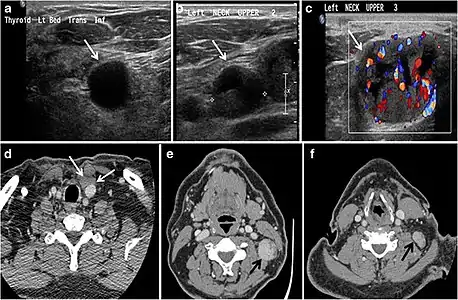

Fig. 9. A 58-year-old male patient with persistence PTC at thyroid bed with hypervascular nodal metastasis. a–c Transverse greyscale and colour Doppler neck ultrasound demonstrate hypoehoic soft tissue in the left thyroid bed (white arrow in a). There are a heterogeneous enlarged lymph nodes at level 2 and 3 with markedly increased vascularity (white arrow in b and c). d–f Enhanced axial CT images of the neck demonstrate a 2.7 × 1.4 cm hypodense soft tissue lesion anterior to the left carotid sheath (white arrow). There are left-sided enhancing abnormal and enlarged lymph nodes at cervical level 2 and 3 (black arrows).[1]